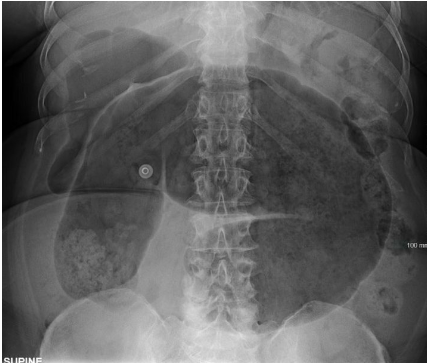

The best course of definitive management for Cecal volvulus is _____